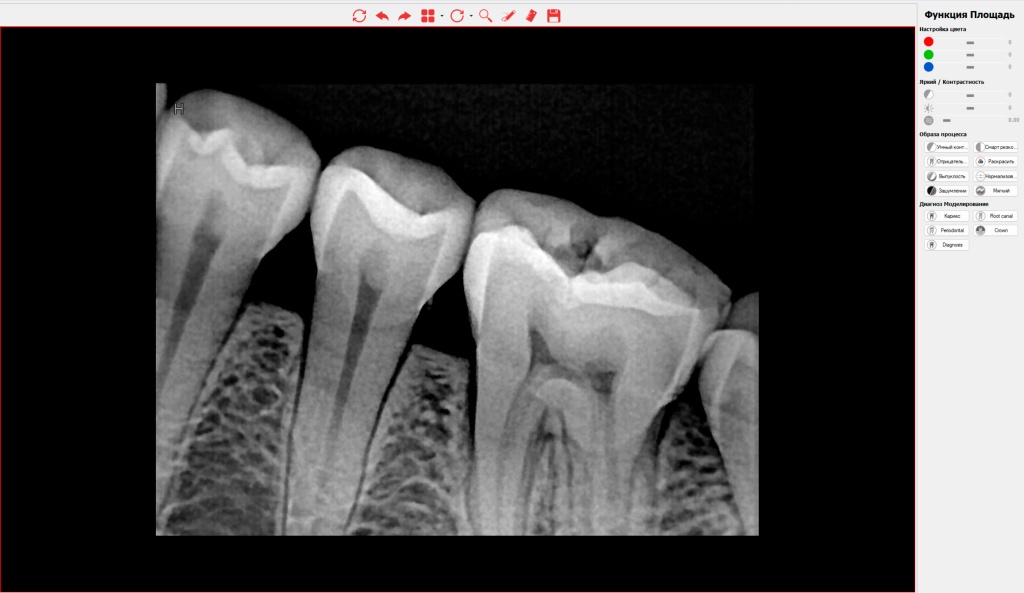

Клинические фильтры изображения

На левой боковой панели сосредоточены алгоритмы улучшения качества рентгенограммы. Если снимок получился излишне темным или светлым (вследствие анатомических особенностей плотности кости пациента), врач может компенсировать это цифровыми фильтрами.

Доступна тонкая настройка яркости, контрастности, инверсия цвета (позитив/негатив), а также применение алгоритма псевдо-рельефа (3D-emboss), который четко очерчивает границы анатомических структур и контуры эндодонтических инструментов в канале.